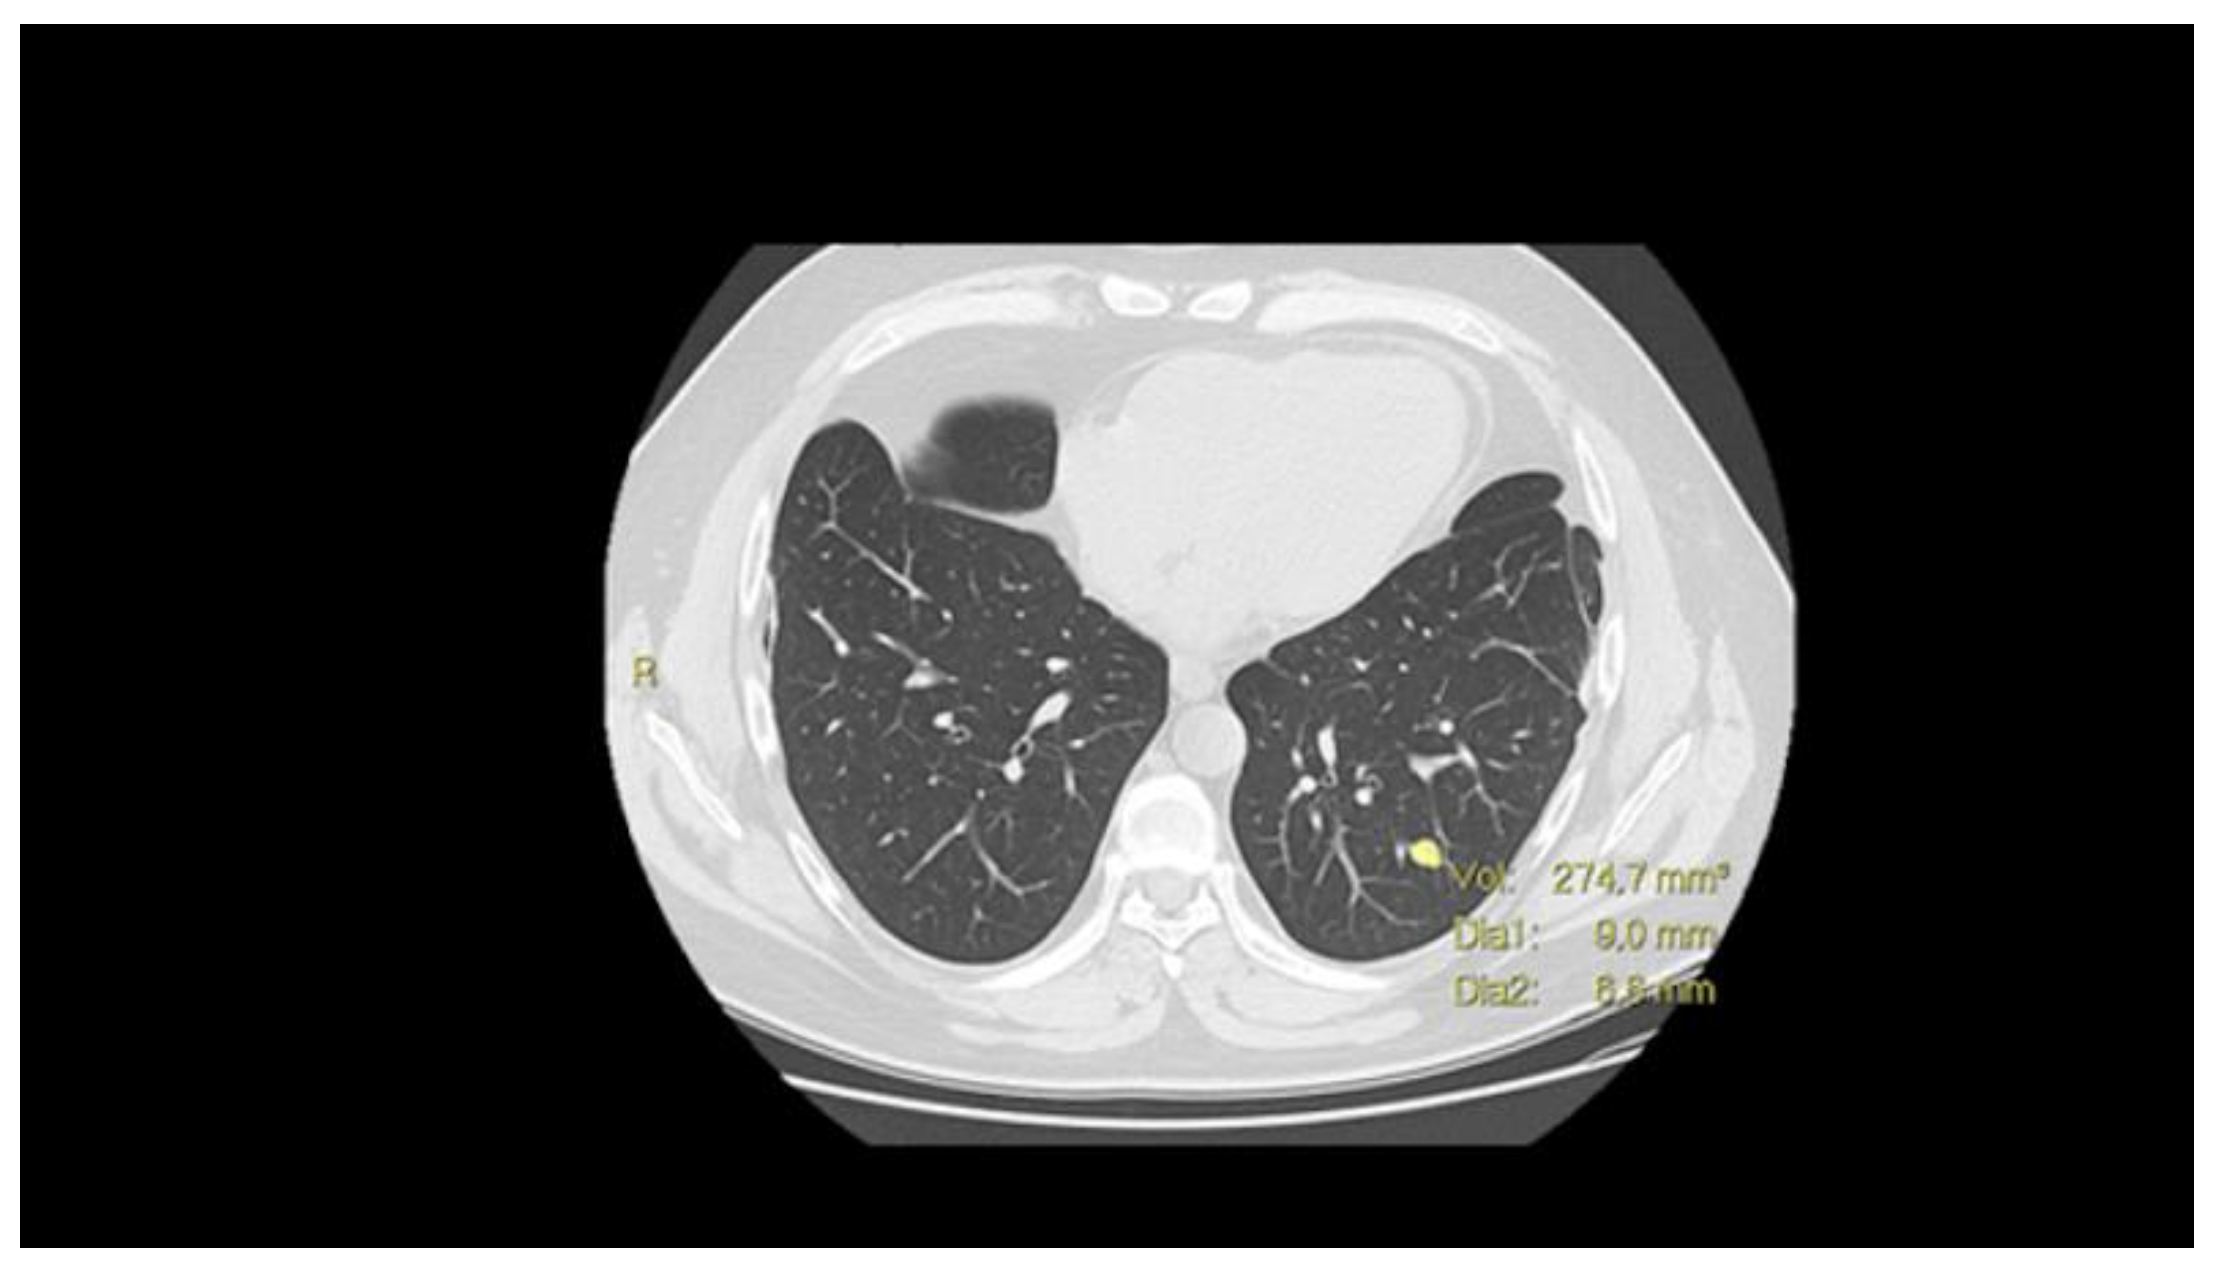

3.3.2. Volume Doubling Time (VDT)

- Hayes, S.A.; Pietanza, M.C.; O’Driscoll, D.; Zheng, J.; Moskowitz, C.S.; Kris, M.G.; Ginsberg, M.S. Comparison of CT volumetric measurement with RECIST response in patients with lung cancer. Eur. J. Radiol. 2016, 85, 524–533. [Google Scholar] [CrossRef]

- Nakamura, T.; Matsumine, A.; Matsubara, T.; Asanuma, K.; Uchida, A.; Sudo, A. Clinical impact of the tumor volume doubling time on sarcoma patients with lung metastases. Clin. Exp. Metastasis 2011, 28, 819–825. [Google Scholar] [CrossRef]